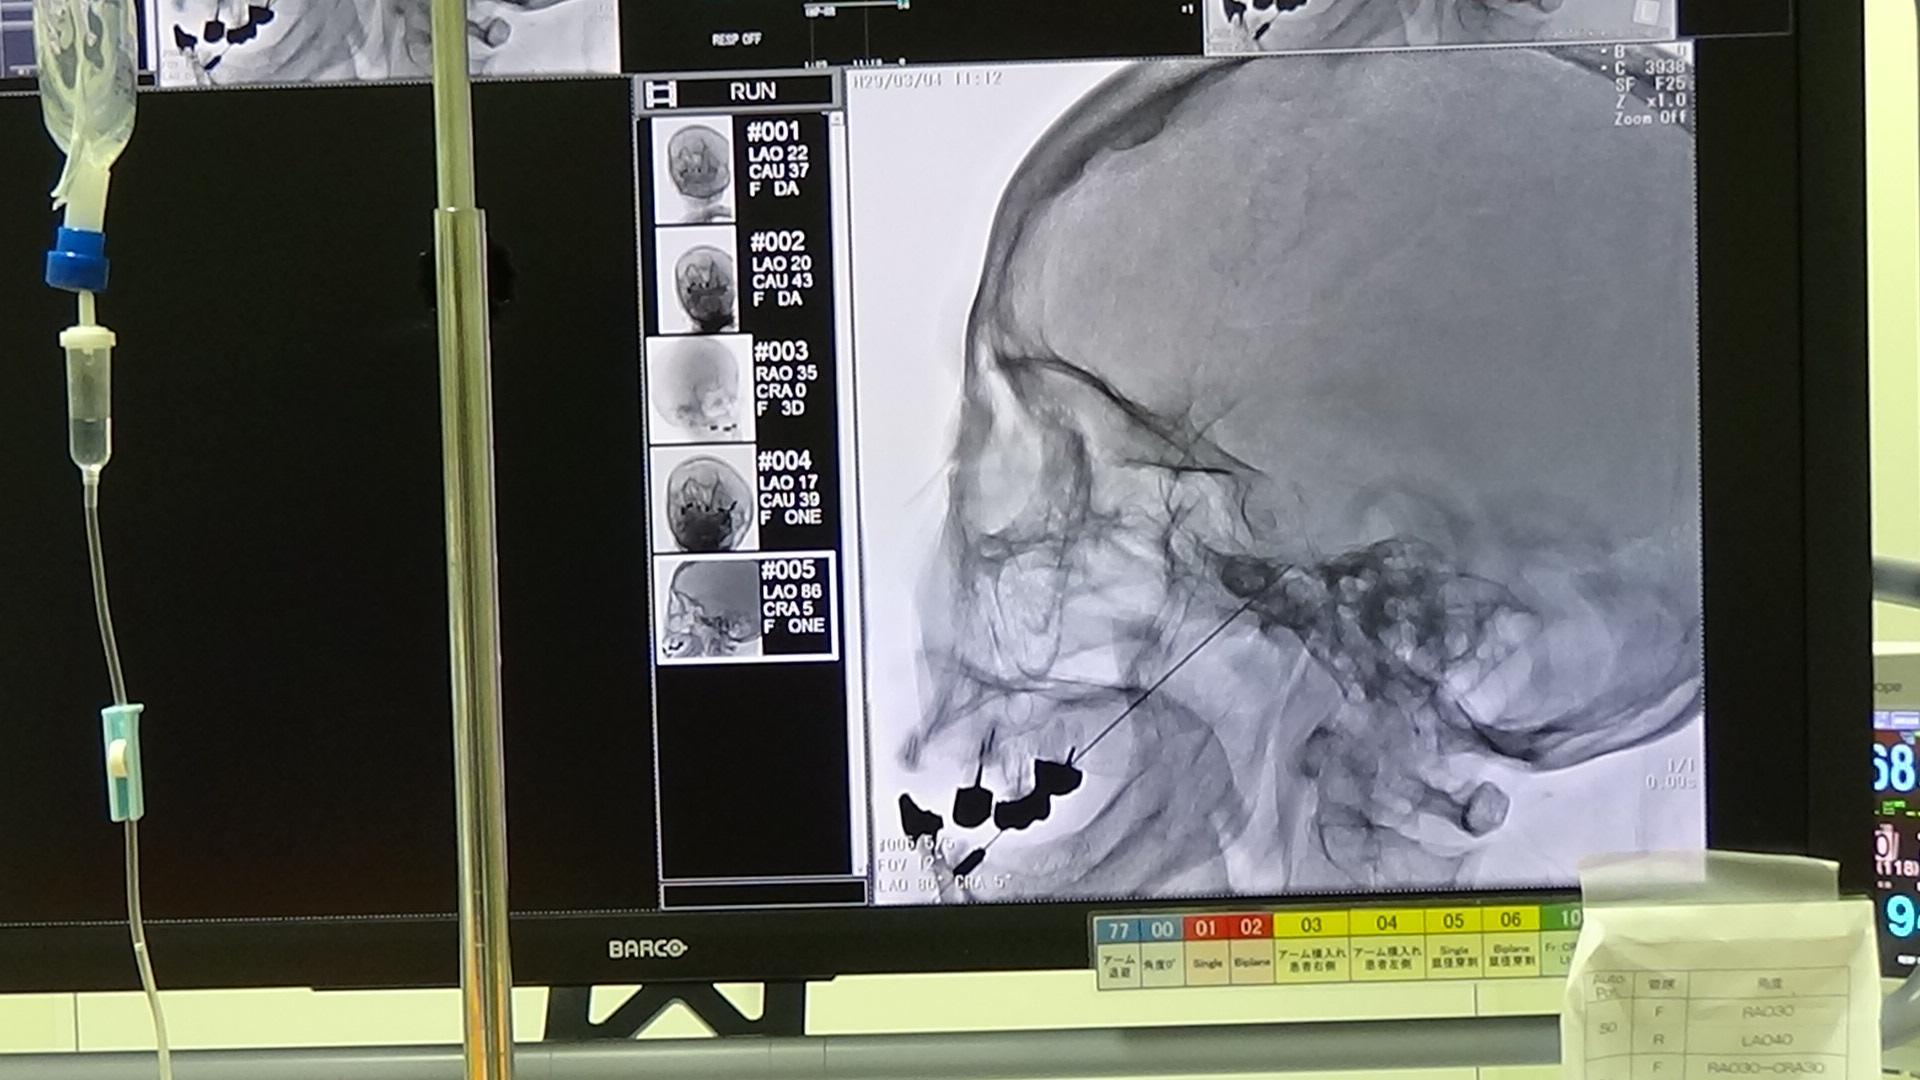

責任基幹施設は、ペインクリニックに関しては東海地方でトップクラスの豊富な症例数を誇る。透視下神経ブロックを積極的に行っており、腹腔神経叢ブロック、ガッセル神経節ブロックなどの難易度の高い神経ブロックは、最新の血管造影装置を使用して、手技中のCT撮像を併用し安全性を高めている。さらに脊髄電気刺激療法など充実したペインクリニック研修が可能である。